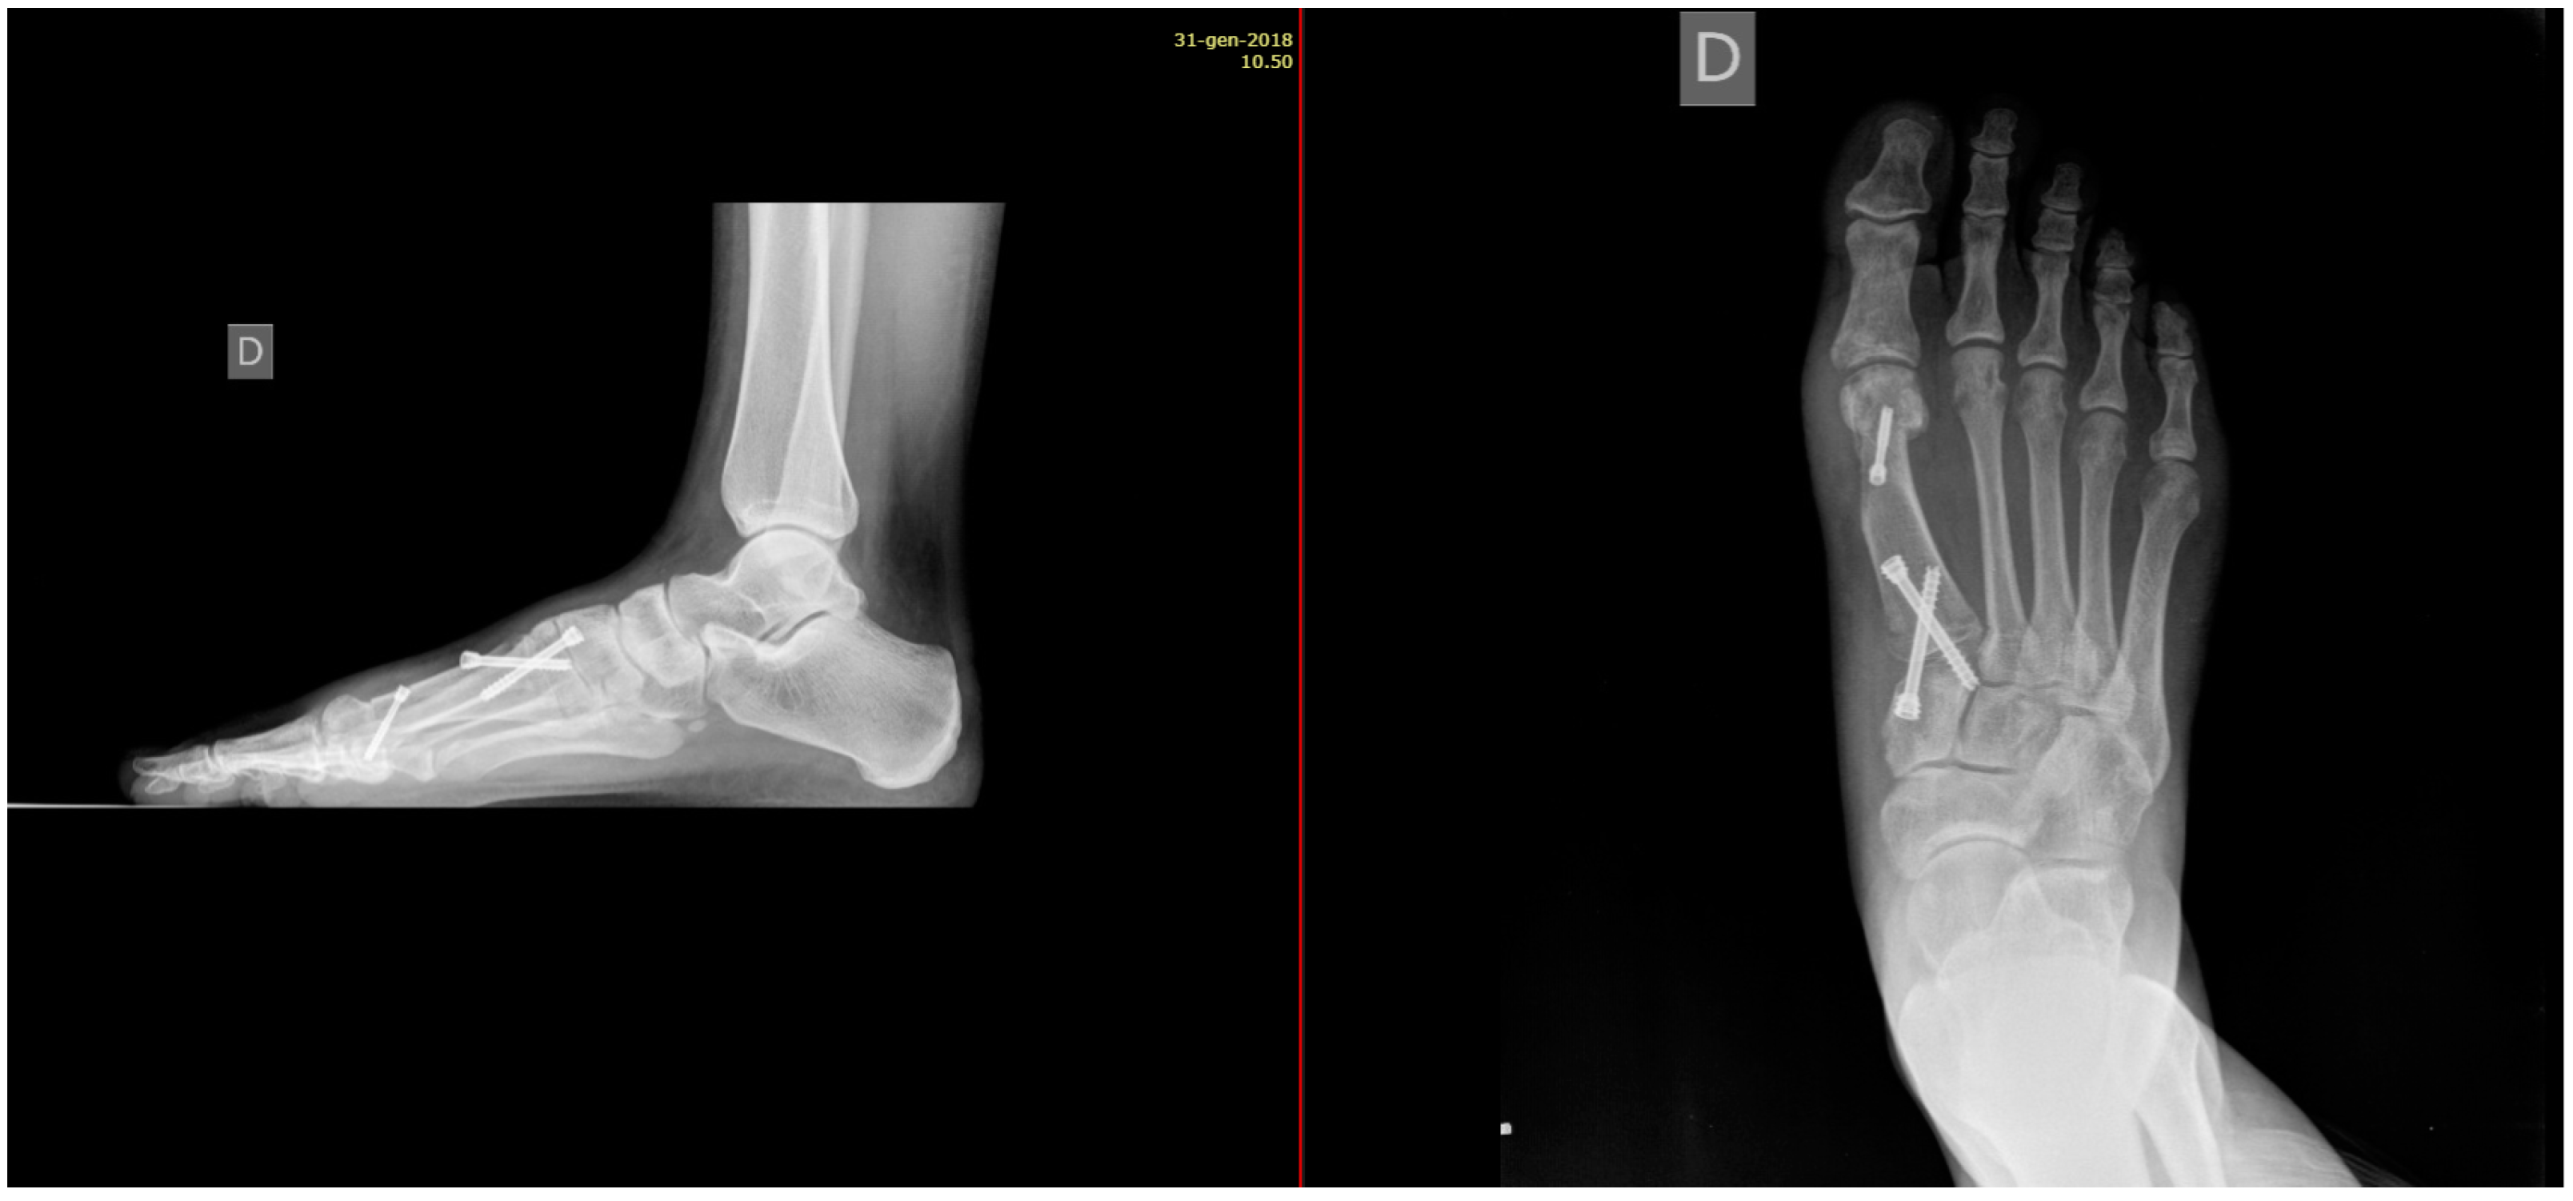

Minimally Invasive Lapidus Arthrodesis Associated with Distal Osteotomy of M1: A Combined Procedure for Hallux Valgus Correction

2. Materials and Methods

Radiographic adequate fusion

| 7 (2) 180 (65) 91 (33) | |

| Medium Shortening | 1.43 mm | |